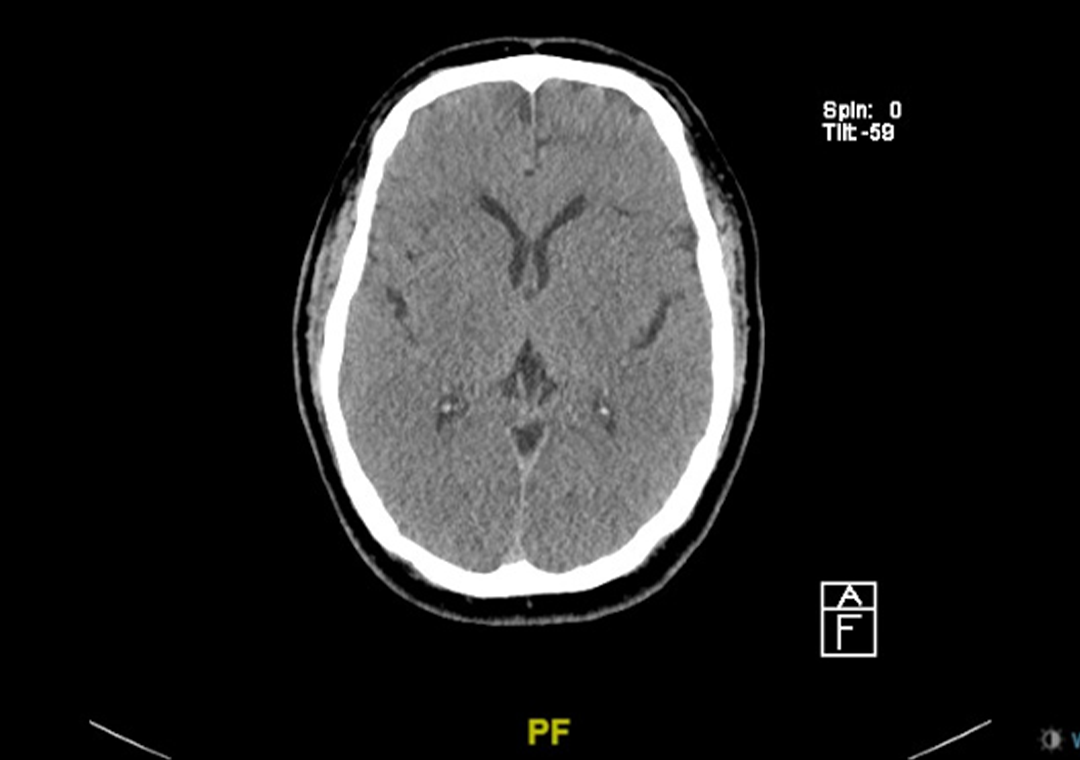

Comparison of diffuse correlation spectroscopy analytical models for measuring cerebral blood flow in adults

Download Document Comparison of diffuse correlation spectroscopy analytical models for measuring cerebral blood flow in adults…